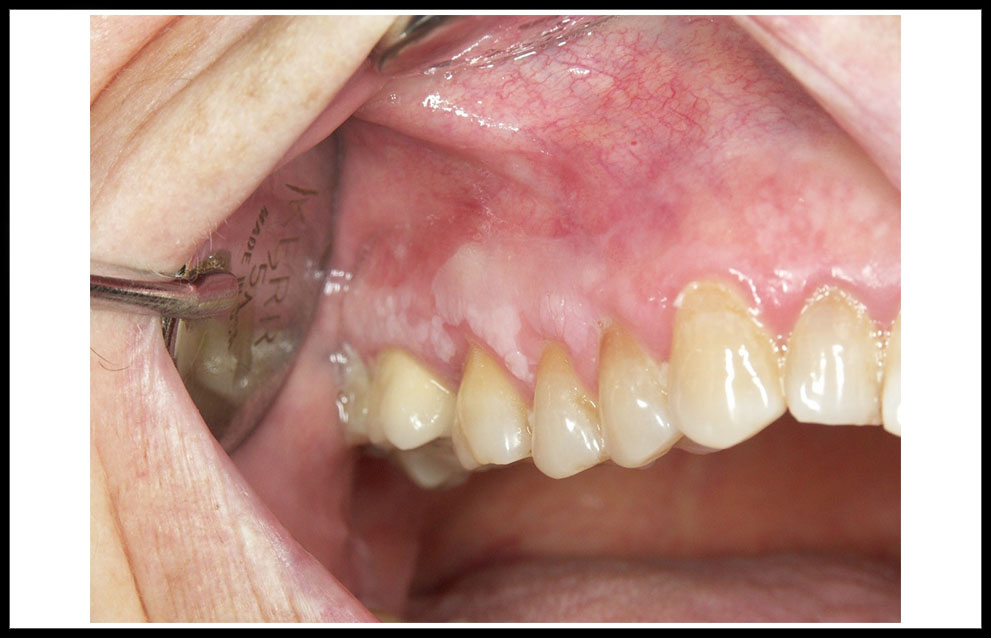

La leucoplasia oral se define como una placa blanca de la mucosa oral que no se desprende al raspado y que conlleva un riesgo de desarrollo futuro de cáncer oral (figura 1). La leucoplasia es la lesión premaligna más frecuente de la cavidad oral. Los estudios epidemiológicos señalan una prevalencia media de leucoplasia oral en el mundo que oscila entre el 1% y el 5% de la población, aunque estas cifras se elevan considerablemente en los países del sudeste asiático y singularmente en la India. Para España y otros países desarrollados de nuestro entorno, probablemente es más razonable aceptar una prevalencia del 0.5%.

Figura 1. leucoplasia oral homogénea localizada en la encía superior

La leucoplasia oral aparecen con una frecuencia algo superior en hombres (6/4), en edades comprendidas entre los 40 y 60 años. Desde el punto de vista clínico, una clasificación clásica considera 4 tipos esenciales der leucoplasia que tienen una correspondencia pronóstica. Las formas homogéneas son placas homogéneamente blancas que pueden presentar pliegues más o menos profundos (figura 1). Las leucoplasias no homogéneas integran a su vez tres subtipos: Las denominadas leucoplasia nodulares retrocomisurales, frecuentemente infectadas por Candida albicans (figura 2); las eritrolecucoplasias, que asocian áreas blancas y rojas (figura 3); y las leucoplasia verrugosas, que presentan una superficie verrugosa con aspecto parecido al de una coliflor (figura 4). Un tipo clínico especial, no incluido en la clasificación precedente, está constituido por la leucoplasia verrugosa proliferativa. Se trata de una lesión blanca que aparece en mujeres de edad avanzada, no fumadoras ni bebedoras, inicialmente limitada, aunque progresivamente expansiva afectando a zonas amplias de la mucosa oral, especialmente la encía y el paladar, y asociada a un riesgo muy elevado de desarrollo tumoral múltiple de cavidad oral (figura 5).